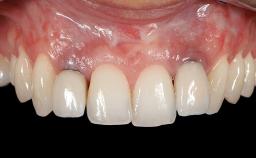

Connective-Tissue Graft to Increase the Width of the Keratinized Mucosa Around an Osseointegrated Implant

Adequate peri-implant soft-tissue thickness is essential not only for esthetic but also for functional reasons. In this case, Vincenzo Iorio Siciliano demonstrates how he achieved increased height and thickness of posterior peri-implant soft tissues to obtain a stable mucosal seal and a width of keratinized tissue favorable to toothbrushing.

The patient, a healthy 38-year-old woman, was referred for increasing the width of the keratinized tissues at the buccal aspect of dental implant 46. The site exhibited a premature-closure screw exposure caused by trauma during chewing, with inadequate keratinized tissue.